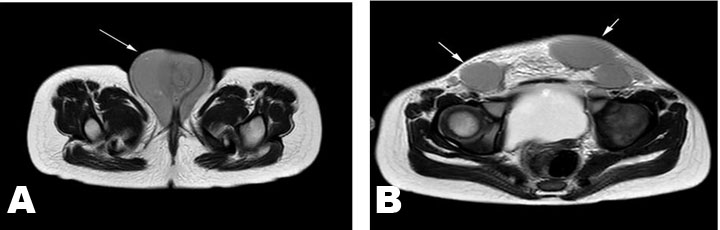

Figure 2: Imaging of intact uterus, vagina, and ovary with MRI. (A) Lymph nodes (25×25 mm) in the bilateral groin area. (B) Bilaterally, the labia majora are infiltrated with a hard consistency.

A 3.5-year-old girl was brought with the complaint of swelling in the vulvar area (The size of the vulvar swelling was 63×63×72 mm). Two years ago, she was diagnosed with infant ALL (CD10 60%, CD19 80%, B ALL, cerebrospinal fluid normal, genetic 15% cells in 11q23) and AALL0631 chemotherapy protocol was applied. While the patient had bone marrow remission in the 6th month of chemotherapy, the parents rejected chemotherapy. Two years after stopping chemotherapy for insufficient duration, the patient was brought with findings of infiltration in the vulvar area (genitomegaly, EMR, and bone marrow in remission). On physical examination, her general condition was good and she was active. The gums, eyes, and other areas of skin were completely normal. Organomegaly was not detected. Starting from the symphysis pubis (Figure 1A), there was soft tissue infiltration with a hard consistency extending to the perineum (Figure 1B). Lymph nodes (25×25 mm) were detected in the bilateral inguinal region (Figure 2A). There were no skin findings other than the genital area. Bilaterally, the labia majora were infiltrated with a hard consistency (Figure 2B). Routine biochemical and preliminary hematological investigations including a peripheral blood smear examination were performed. White blood cell count (WBC) 9.620/mm3, hemoglobin (Hb) 12.8 g/dL, and platelet count (Plt) 366×109/L were detected. In the peripheral smear, the eosinophil rate has increased by 11% and no blasts were observed. Lactate dehydrogenase (LDH) 310 U/L and uric acid were determined to be normal. Abdominal and pelvic ultrasonography revealed multiple lymphadenopathies in the right inguinal region, the largest of which was 55×37 mm in size, had thinned fatty hilus, was obliterated, had a prominent thick cortex, and contained cortical heterogeneity. Uterine, vaginal, and ovarian imaging was evaluated as normal. No blasts were observed in bone marrow aspiration and biopsy. 22% eosinophils were observed in the bone marrow.

Magnetic resonance imaging (MRI) revealed an intact uterus, vagina, and ovary (Figure 2A and Figure 2B). In positron emission tomography/computed tomography (PET/CT), starting from the anterior of the symphysis pubis; increased fluorodeoxyglucose (FDG) uptake at the level of malignancy (SUVmax: 4.2) was detected in the soft tissue density mass (55×56×70 mm at its widest point) extending to the perineum (skin and subcutaneous), involving the bilateral labium majus, and having no boundaries with the vagina. The bladder and ureters were dilated and hydropic. It was evaluated as a PET/CT study compatible with malignant (SUVmax: 4.5) lymph nodes in the bilateral inguinal region, the largest of which was measured as 30×27 mm. Spleen and liver SUVmax (respectively 1 and 1.2) values were normal for her age (Figure 3A and Figure 3B). Biopsy from the genital area showed ALL infiltration into the skin and subcutaneous tissue with the same phenotype as the primary disease (proliferation of ALL cells). Reinduction chemotherapy was immediately started. Our patient was included in the bone marrow transplant program. During this period, the patient’s treatment was completed successfully.